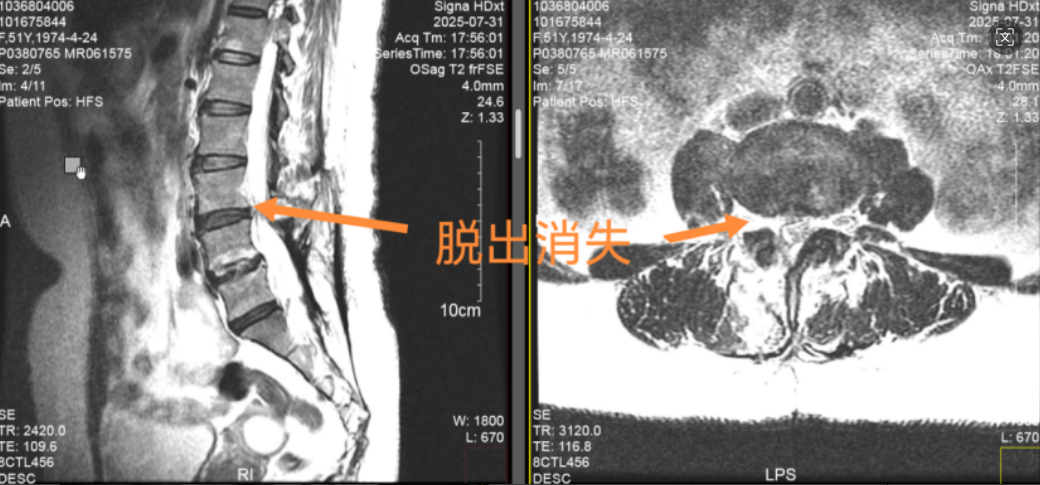

(▲术后张阿姨复查核磁共振图,可见明显好转,突出消失)

张阿姨的MRI显示,L3/4椎间盘向右外后上方突出,正是压迫神经的“罪魁祸首”。